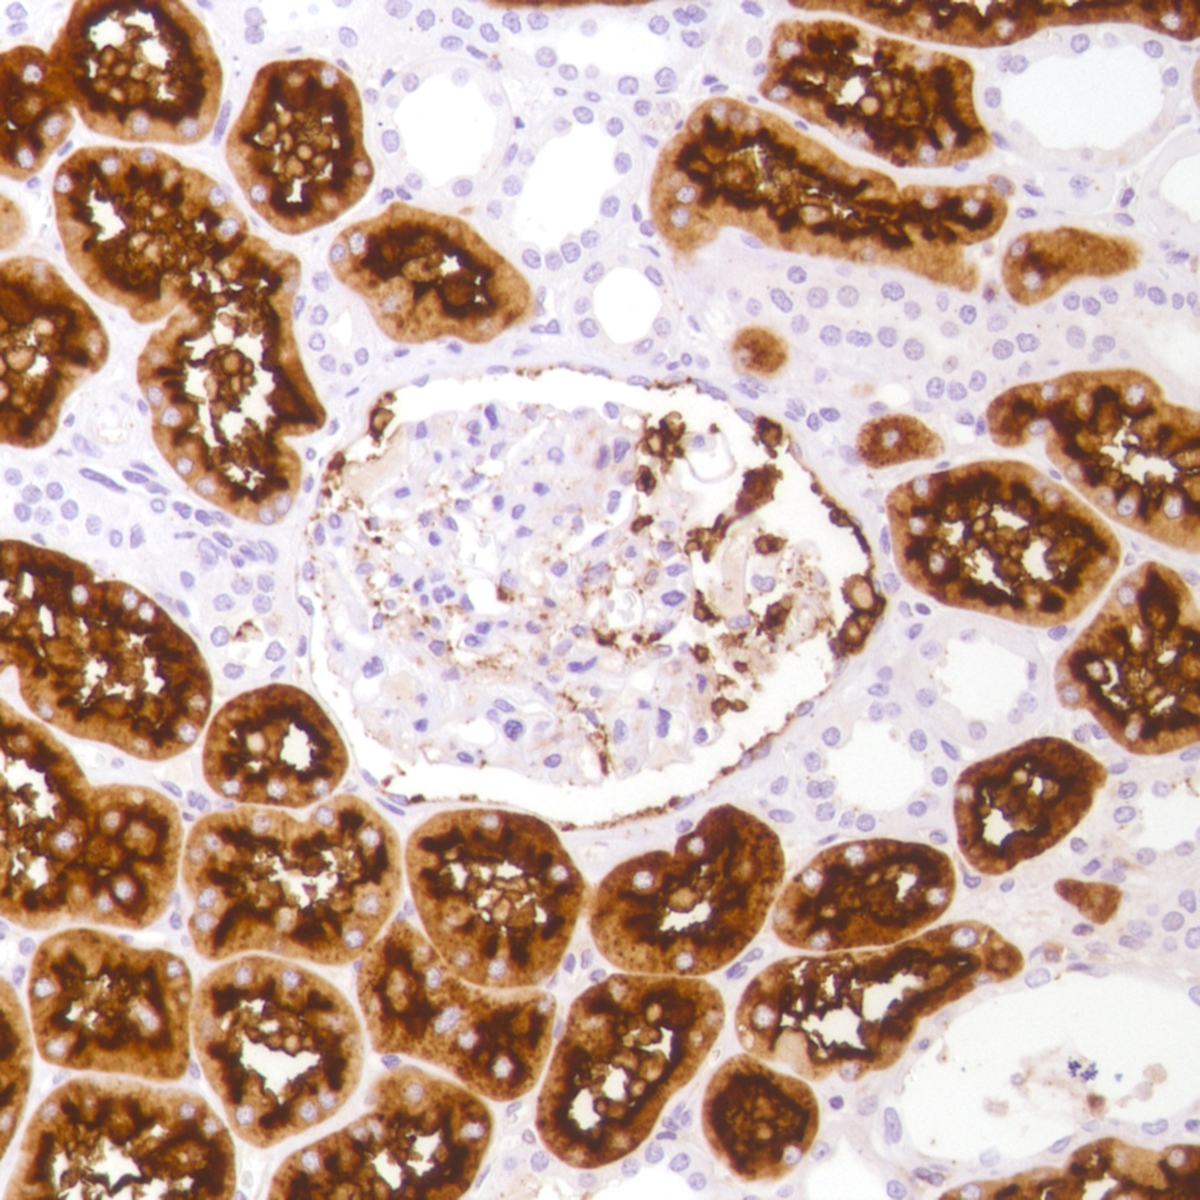

CD13 (SP182)

CD13, also known as aminopeptidase N, participates in the final digestion of peptides from stomach, pancreas, and other organs. It expresses by diverse cell types including small intestinal and tubular epithelial cells, macrophages, granulocytes and synaptic membranes. It may be involved in the cleavage of antigen peptides, degradation of neurotransmitters, and angiogenesis. It is one of the useful markers for acute myeloid leukemia or lymphoma.